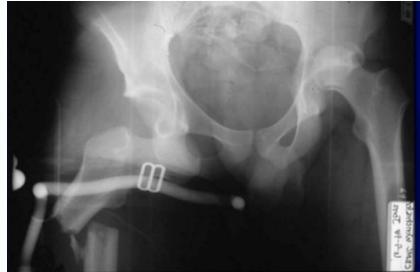

Posterior Hip Dislocation

Clinical Picture:

- Pain, Inability to move hip

- On examination: Limb is short, adducted, internally rotated & slightly flexed

Must Rule-out:

- Sciatic nerve injury

- Associated fractures:

- Femur or acetabulum

- Patella

Imaging:

- X-ray & CT scan

- R/O an acetabular fracture (or intraarticular bony fragment)